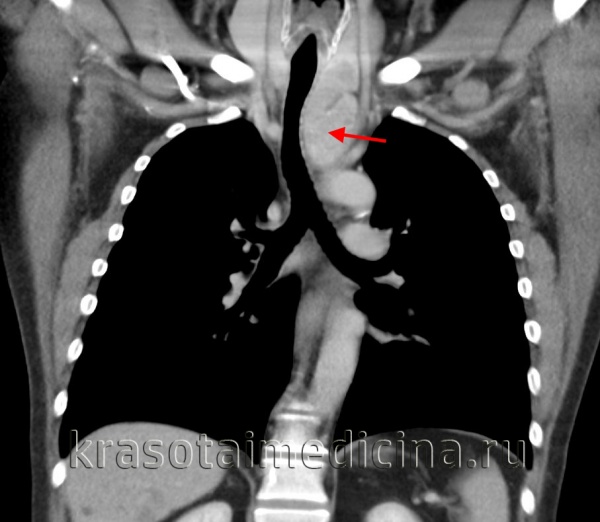

(а) У мужчины 30 лет на совмещенных изображениях при нативной КТ (вверху) и ФДГ-ПЭТ/КТ (внизу) в правой половине преваскулярного отдела средостения определяется объемное образование, интенсивно поглощающее ФДГ. При биопсии под контролем КТ была подтверждена медиастинальная семинома.

(б) Мужчина 42 лет через четыре года после проведения химиотерапии по поводу медиастинальной семиномы. При КТ с контрастным усилением визуализируется отсутствие роста и контрастирования мягких тканей. При ПЭТ/КТ признаки метаболической активности также не были выявлены. После химиотерапии или лучевой терапии по поводу семиномы часто наблюдается резидуальная мягкотканная структура.